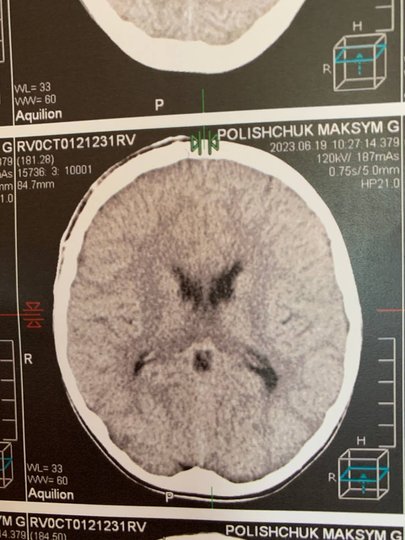

За оцінками лікаря, операцію потрібно було проводити негайно, оскільки через гематому ділянка мозку, на яку тиснув кров’яний згусток, могла почати відмирати. Оперативне втручання розпочали близько 23:00, тривало воно впродовж 3,5 годин.

– Особливість цієї операції в тому, що це була велика гематома. Ми йому зняли невеликий фрагмент кістки, забрали гематому, і після цього кістку поставили назад і прифіксували спеціальними кістковими швами. Завдяки цьому в нього все швидко заросте і не буде косметичного дефекту, – зазначає Сергій Романчук.